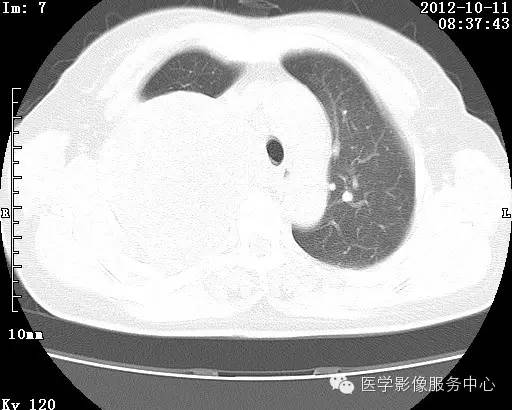

【病例】右肺巨大错构瘤1例CT影像表现

病史:女 65岁咳嗽咳痰 右肺巨大肿块就诊。

错构瘤的主要组织成分包括软骨、脂肪、平滑肌、腺体、上皮细胞,有时还有骨组织或钙化。错构瘤一般为实质致密的球形、卵圆形,也可以是分叶状或结节状,大多数直径在3cm以下。

错构瘤的发病年龄多数在40岁以上,男性多于女性。 绝大多数错构瘤(约80%以上)生长在肺的周边部,紧贴于肺的脏层胸膜之下,有时突出于肺表面。其特征钙化为爆米花样钙化,内有脂肪软骨成分等等。最常见的部位是胸膜下肺实质内,其次为主支气管或肺叶、肺段支气管内。

瘤内出现“爆米花样钙化”是诊断的主要指标之一。早期的点状、斑片状及结节状钙化 随时间增加钙化数量及范围会增加,最终可能演变 为爆米花样钙化;